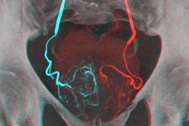

Theo Bệnh viện Nguyễn Tri Phương, tuyến tiền liệt là một cơ quan nhỏ có kích thước khoảng 2cm đường kính, nằm dưới bàng quang (nơi chứa đựng nước tiểu) và bao bọc xung quanh niệu đạo (là ống dẫn nước tiểu ra khỏi bàng quang). Chính vì tuyến bao quanh niệu đạo nên nếu bị phì đại tuyến tiền liệt sẽ gây cản trở dòng nước tiểu từ bàng quang ra niệu đạo; làm xuất hiện các triệu chứng rối loạn về tiểu tiện (tiểu khó, tia nước tiểu yếu, tiểu dắt, tiểu đêm nhiều lần…).

Hiện nay cắt bỏ tuyến tiền liệt qua đường niệu đạo là phương pháp được sử dụng nhiều nhất. Trong loại phẫu thuật này, chỉ một phần của tuyến tiền liệt bị loại bỏ. Sau khi được gây tê, một dao cắt được đưa qua dương vật.

Bác sĩ sẽ dùng dao cắt với một dây quang học đặc biệt hoặc chùm laser để loại bỏ từng phần tổ chức gây tắc nghẽn. Những phần bị cắt bỏ được đưa vào bàng quang dưới dạng lỏng và sau đó được loại bỏ ra ngoài khi kết thúc phẫu thuật.

Mổ hở là phương pháp phẫu thuật lâu đời nhất để hỗ trợ điều trị u xơ tuyến tiền liệt. Các bác sĩ ít khi áp dụng phương pháp này nhưng nó vẫn là lựa chọn được ưu tiên nếu u xơ tuyến tiền liệt có kích thước quá lớn. Sau khi được gây tê, bác sĩ sẽ mở một đường rạch để tiếp cận với vỏ tuyến tiền liệt và nạo phần tổ chức bị phì đại từ phía trong của tuyến tiền liệt.